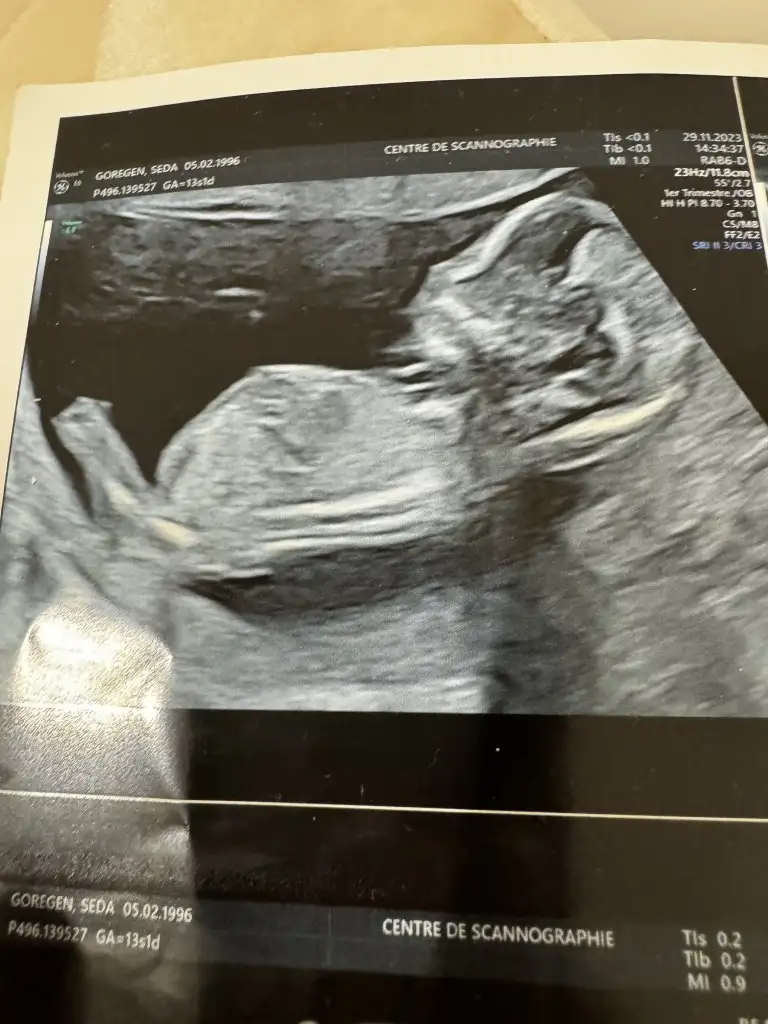

Hayır öğrenemedim maalesef yurt dışındayım geç söylüyorlar burda 13 haftalıkken gittim erkeğe benziyor ama emin değilim dediKız bence cnm öğrendin mi cinsiyetini

Birde bunlara bakar mısın canım yurt dişnda geç söylüyorlar henüz öğrenmedim meraktan patlicam vallaGerçi kız gibi de. 2. Fotoya bakacaksınız o çıkıntının sırt ile olan açısına bakılıyır

Ya hiç göstermemiş ki nub kısmını. Erkek gibi geldi ama emin olamadım.Birde bunlara bakar mısın canım yurt dişnda geç söylüyorlar henüz öğrenmedim meraktan patlicam valla

Canım alın kısmı düzse erkek bombeliyse kız diye biliyorum erkeğe benziyo benceSiz söyledikçe dikkat ediyorum gerçekten öyle mi acaba